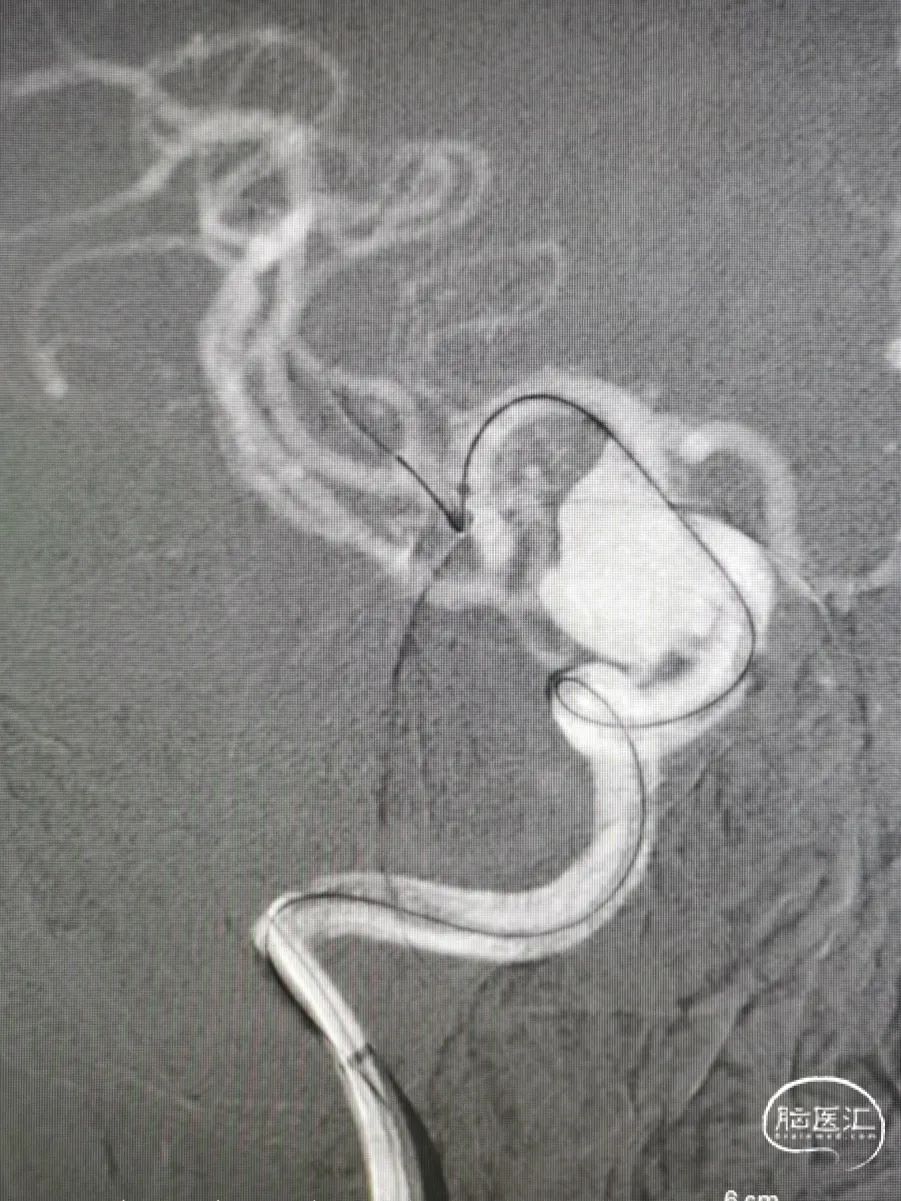

图4右颈内动脉海绵窦段起始部类圆形瘤样扩张,最大约19mm╳14mm,瘤颈约14mm,瘤内射流明显,载瘤动脉远端5mm,近端4.5mm。

8F常规指引到右颈内动脉开口做近端支撑。Synchro 0.014 200微导丝及XT-27微导管引导CAT 5导管同轴越过右颈内动脉瘤至右大脑中动脉M1。由于动脉瘤颈较大,微导丝引导XT-27微导管,无法直接通过,采用瘤内成袢技术通过。选取Surpass Streamline 5mm╳30mm经CAT 5导管释放,并行微导丝及CAT 5导管按摩。

图5

术后造影

术后对比瘤内喷射征明显减少,造影剂滞留明显。行CT重建提示支架贴壁良好,术后顺利复苏,4天后顺利出院。

图6